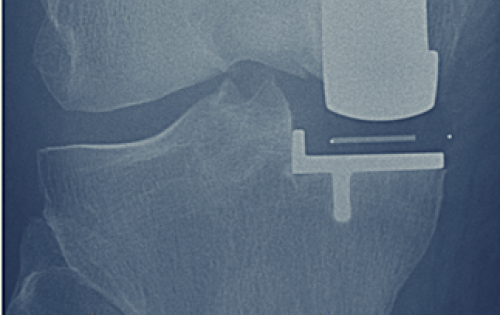

Photo of Knee Joint